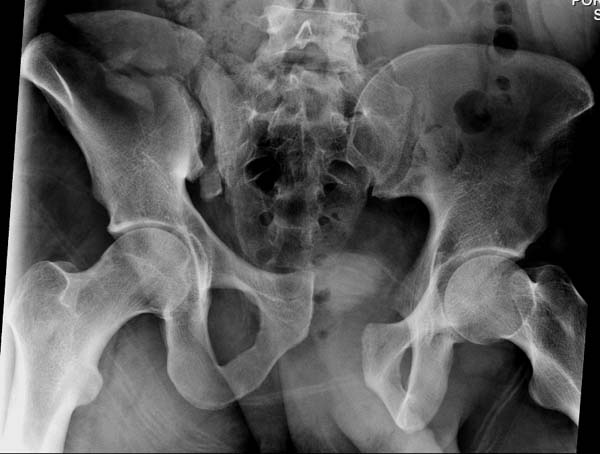

Перелом заднего отдела крыла подвдошной кости доказывает, что задние

связочные элементы подвздошно- крестцового сочленения интактны, и такой

перелом известен как“Сrescent fracture’. Переломы разделяется на 4 типа,

и до фиксации надо хорошо изучить топографию перелома, иначе винт может

попасть в линию перелома и не удержать фиксацию.